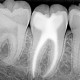

Su diagnóstico precoz es fundamental y se realiza mediante un estudio clínico visual, un sondaje y estudio radiográfico exhaustivo de todos los dientes (Diagnóstico Periodontal).